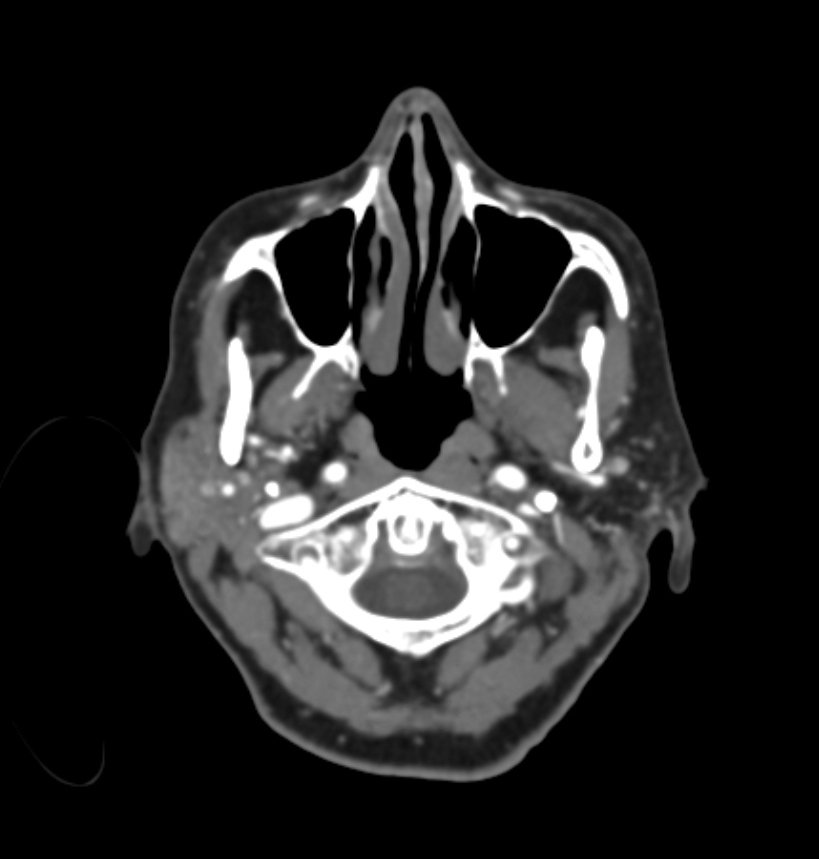

MRI combined with image processing pipelines provide a powerful tool to inform doctors how to treat arrhythmias. Visualizations can help providers plan intervention and then to communicate findings and care plans to the patient.